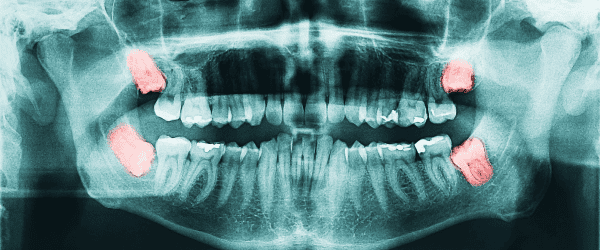

We begin with a thorough exam and digital x-rays to check the position of your wisdom teeth and determine if extraction is needed.

Extractions are necessary when a tooth is severely damaged by decay, crowding prevents new teeth from erupting, baby teeth don’t fall out in time, wisdom teeth are impacted, or when severe infection persists despite treatment.

There are two main types: simple extractions for teeth visible above the gum line, and surgical extractions, such as wisdom tooth removal, for teeth that cannot be easily accessed.